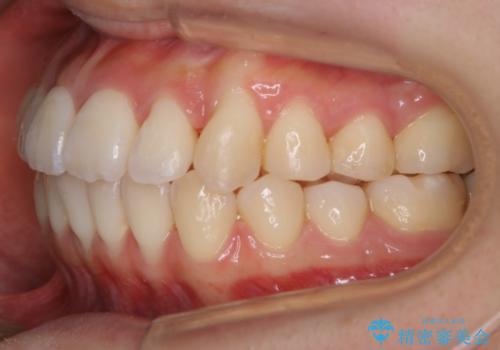

- 上下の歯のガタつきを主訴にご来院されました。

前歯部に特にガタつきが見られ、正中もズレている状態でした。

矯正装置の希望がインビザラインだったため、マイクロインプラントを併用し、奥歯から順に遠心移動をかけていくことにより非抜歯でも主訴のガタつきを治すことができました。

術前・術後の笑った時の歯の見え方の変化にも注目してみてください!